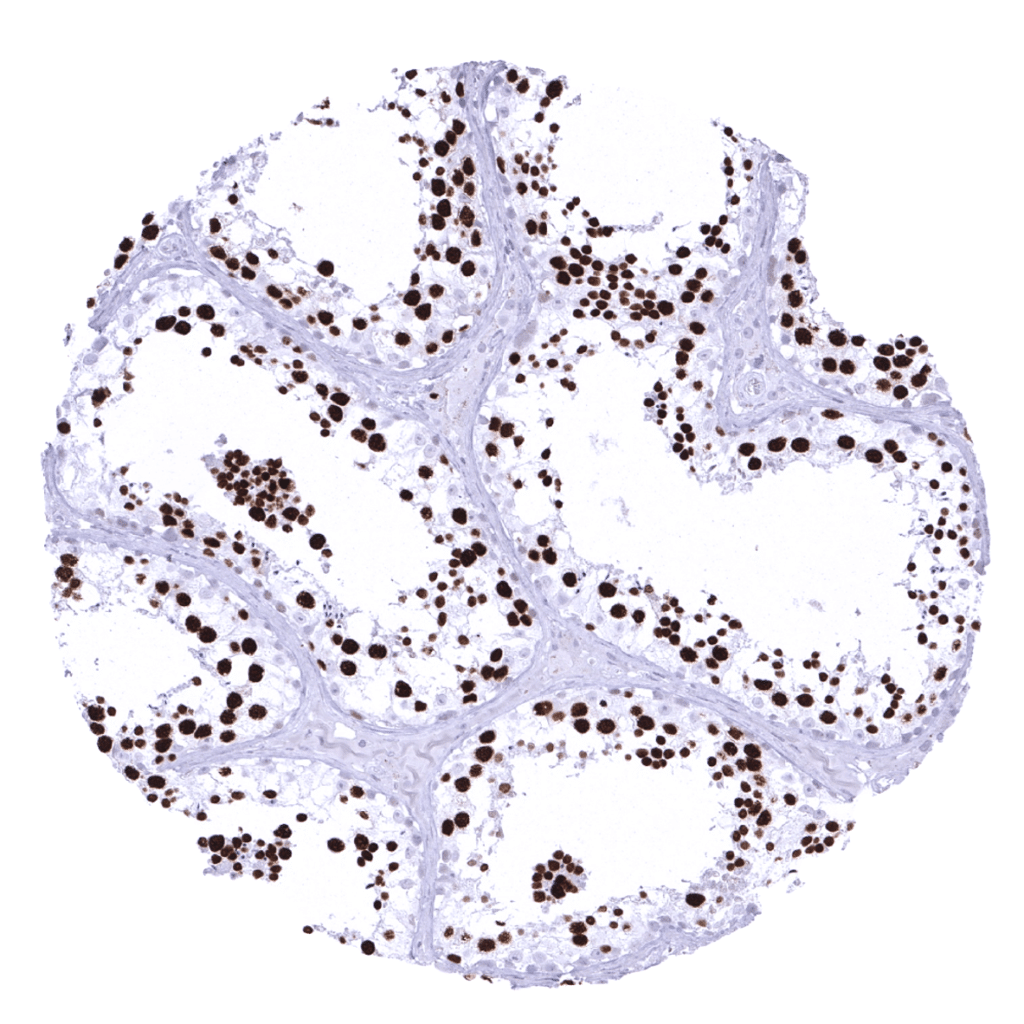

Positive control = Colon: A fraction of cells, especially in the crypt basis should show a moderate to strong nuclear TOPO2A immunostaining.

Staining Pattern in Normal Tissues

In normal tissues, TOPO2A immunostaining can regularly be seen in the vast majority of organs with a distribution pattern consistent with proliferating cells. Accordingly, the pattern largely parallels the display of Ki67 immunostaining. Spermatocytes of the testis – in which a special type of cell division occurs (meiosis) – is the only normal cell type with a consistent strong TOPO2A expression in virtually all cells albeit Ki67 is hardly seen in parallel sections.

Suggested positive tissue control: Colon: A fraction of cells, especially in the crypt basis should show a moderate to strong nuclear TOPO2A immunostaining.

Suggested negative tissue control: Colon: Epithelial cells must not show any TOPO2A staining in the cytoplasm and in most nuclei of the surface epithelium.